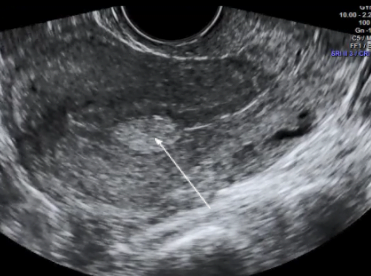

O diagnóstico do pólipo endometrial na maior parte das vezes é realizado por meio do ultrassom transvaginal.

É muito importante para o diagnóstico do pólipo endometrial, que a mulher esteja na primeira fase do ciclo menstrual, ou seja antes da ovulação, pois facilita o diagnóstico pela ultrassonografia.

Os melhores dias para a realização do ultrassom transvaginal para diagnóstico do pólipo é entre o 6° e o 12° dia do ciclo menstrual, lembrando que o primeiro dia da menstruação é o primeiro dia do ciclo.

Quando o exame é realizado após a ovulação, é possível que a ultrassonografia não identifique o pólipo, ou tenha dúvidas quando ao diagnóstico e, nesta situação, deve-se repetir o exame após a menstruação.

Menopausa, tamanho do pólipo, espessura endometrial, tipo e intensidade de vascularização e a história clínica são fatores que devem ser avaliados e que contribuem para o risco de malignidade.